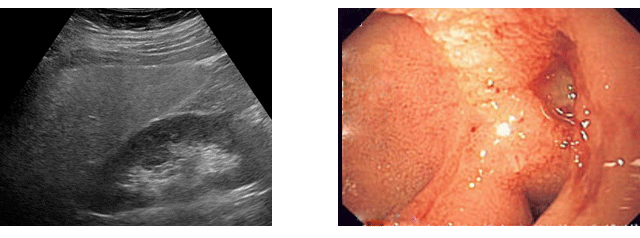

¼Òȱâ Áúȯ

Áø·á½Ç¿¡¼ ¸¸³ª°Ô µÇ´Â ¸¹Àº ȯÀÚµéÀÌ ¼ÒȺҷ®, º¹Åë, ¼³»ç ±×¸®°í º¯ºñ µîÀÇ ¼Òȱâ Áõ»óÀ» È£¼ÒÇϸç, ½ÇÁ¦·Î ¿ì¸®³ª¶ó´Â À§¾ÏÀÇ ºóµµ³ª ¼Òȼº ±Ë¾çÀÇ ¿øÀαÕÀÎ Ç︮ÄÚ¹ÚÅÍÀÇ °¨¿°À²ÀÌ ¼¾ç ±¹°¡µéº¸´Ù ¿ùµîÀÌ ³ôÀº ³ª¶óÀÔ´Ï´Ù. ¼ÒȰ¡ ÁúȯÀº ±¸°ºÎÅÍ Ç×¹®±îÁö ¼Òȱâ´ÉÀ» ´ã´çÇÏ´Â ±â°üµé°ú °£, ´ã³¶, ÃéÀå µîÀ» Æ÷ÇÔÇÏ¸ç ¿©±â¿¡¼ ¹ß»ýÇÏ´Â ¸¹Àº Áúº´À» Áø´ÜÇϰí Ä¡·áÇϰí ÀÖ½À´Ï´Ù.